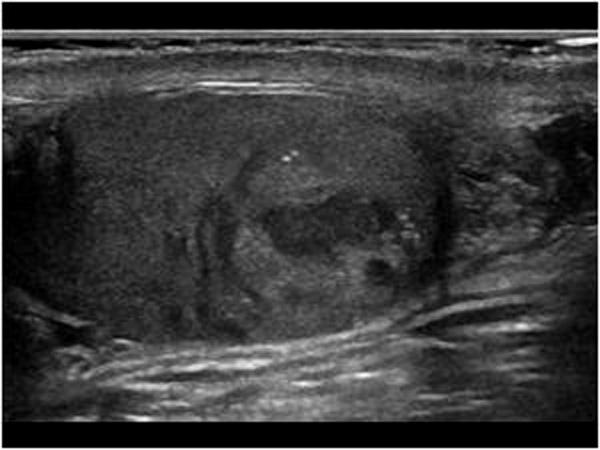

Pancreatic Psydocyst

Spherical fluid collection of pancreatic enzymes that arise from inflamatory, necrotic and hemorrhage processes of the pancrreas

persistently elevated amylase and lipase

Pancreatic Psydocyst

Spherical fluid collection of pancreatic enzymes that arise from inflamatory, necrotic and hemorrhage processes of the pancrreas

persistently elevated amylase and lipase

Pancreatic Psydocyst

Spherical fluid collection of pancreatic enzymes that arise from inflamatory, necrotic and hemorrhage processes of the pancrreas